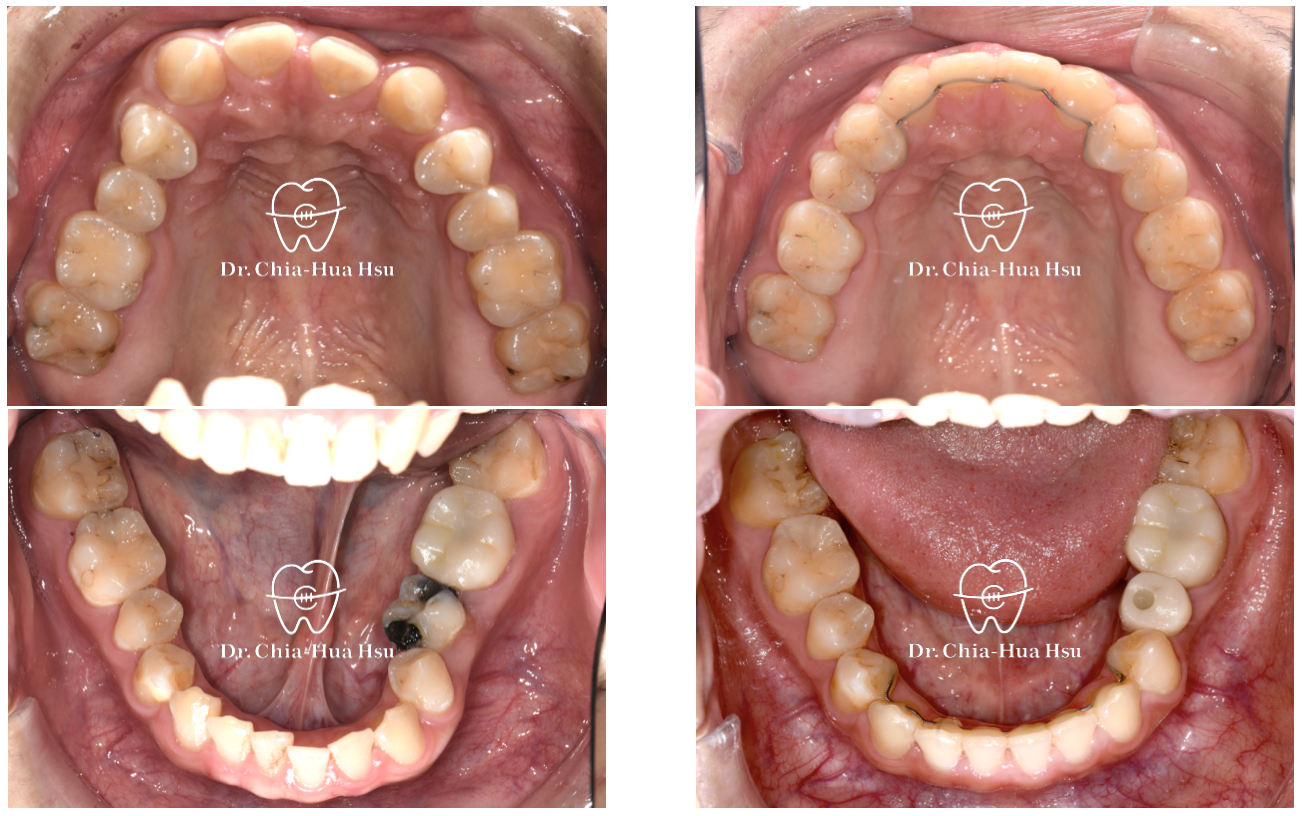

• 問題分析:患者除了門牙牙縫、齒列不正問題,有先天性缺失上顎雙側側門牙兩顆以及左下第二小臼齒,並且左下方有滯留的乳臼齒,治療難度高。

• 治療方式:使用傳統金屬矯正器,並搭配拉口內橡皮筋的方式來讓上顎後排牙齒往前移動,以關閉缺牙縫隙。

• 治療結果:改善缺牙、縫隙,以及上下顎咬合關係,左下乳臼齒拔除後以一顆植牙重建。